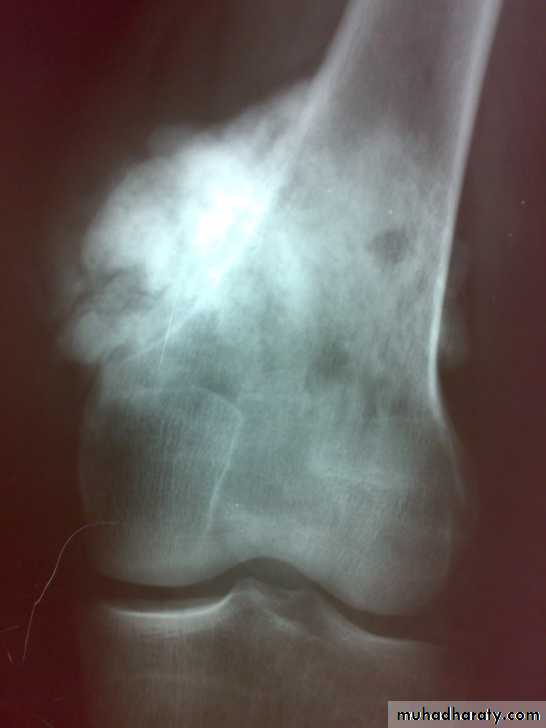

X-ray show eccentric osteolytic lesion in the end of long bone ,subchondral, trabeculated (soap bubble appearance). The cortex is thin, expanded or even perforated.